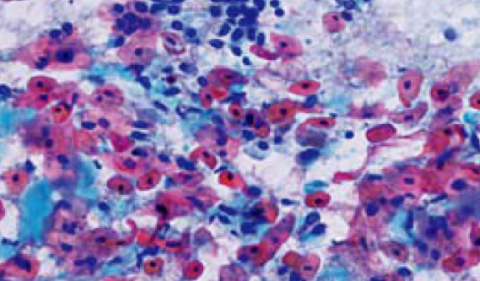

化生(metaplasia)是指一种分化成熟的组织被另一种分化成熟的组织取代的过程。

化生是局部组织在病理情况下的一种适应性表现,在一定程度上对人体可能是有益的。鳞状上皮的化生能增强粘膜的抵抗力,使粘膜在不利的情况下仍能生存。

有时化生的细胞可以发生恶性肿瘤。但支气管柱状上皮发生鳞状上皮化生时,丧失了纤毛,削弱了呼吸道的防御功能使易受感染。